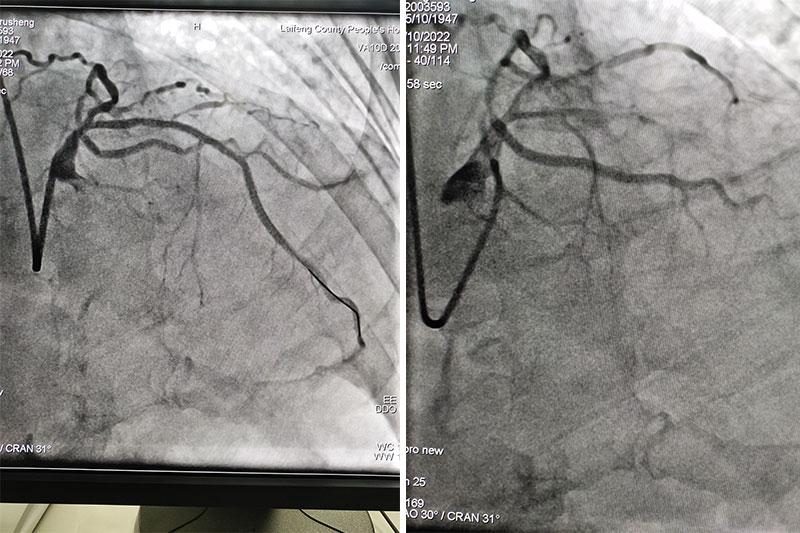

2022年02月10日,来凤县人民医院紧急再次为一74岁老年男性绕行CCU行急诊冠状动脉造影、冠状动脉支架植入术,成功挽救了患者的生命!

该患者突发胸痛3小时来到我院就诊,我院胸痛中心立即启动胸痛救治流程,一路绿色通道畅行,患者16:32分进入我院就诊,16:34分急诊科郑振亮主任接诊,通过问诊,快速锁定为高危胸痛患者,随时有死亡风险,16:38分完善心电图,提示急性前壁心肌梗塞,给与心梗一包药,上传心电图到胸痛中心微信群,立即拨打我院胸痛中心值班电话19172430198,胸痛中心值班医师杨继成医师立即电话至导管室请示是否启动急诊PCI术,此时我院导管室刚好做完最后一台择期手术,恩施慧宜医疗集团张宏伟教授及我院心内科副主任朱兴彪主治医师评估患者情况后,16:46分再次激活导管室,16:50分启动导管室,取得家属知情同意后,17:04分送入导管室,17点32分导丝通过了闭塞血管,植入了两枚支架,患者血管再通,胸痛逐渐缓解,此次急诊处理再次充分体现我院胸痛中心建设流程的常态化,从进入我院大门到血管再通仅用了60分钟,进一步为患者救治缩短了时间,挽救了更多的心肌!